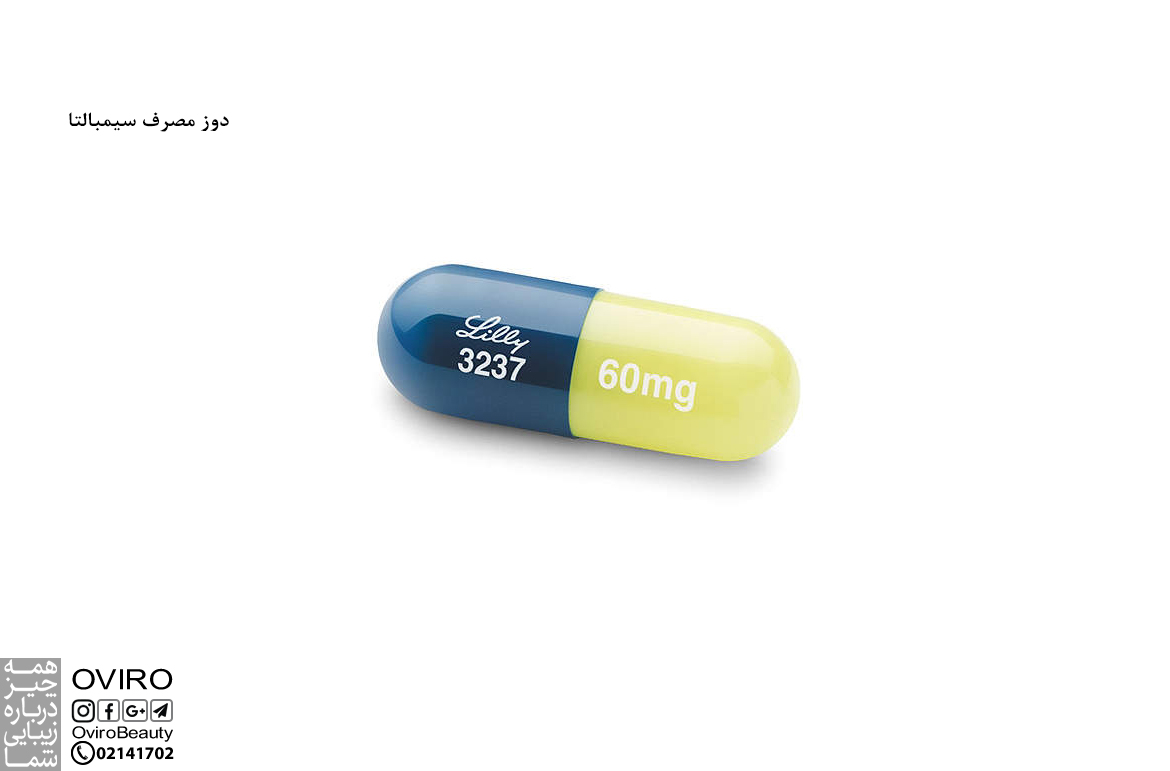

دوز مصرف سیمبالتا

سیمبالتا نوعی داروی ضد افسردگی است که برای موارد مختلفی مانند فیبرومیالژیا و افسردگی بالینی کاربرد دارد؛ دوز مصرف این…